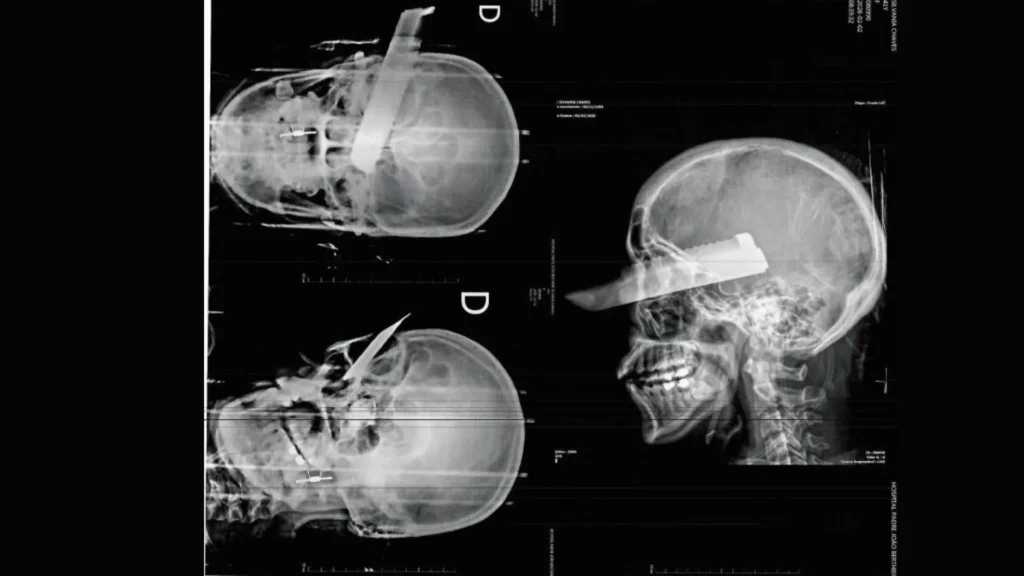

“A faca chegou a atravessar o crânio da mulher e sair pelo olho”, informaram os Bombeiros.

Imagens divulgadas pela polícia mostram o raio-X com a faca cravada na cabeça, ilustrando a gravidade do ataque.